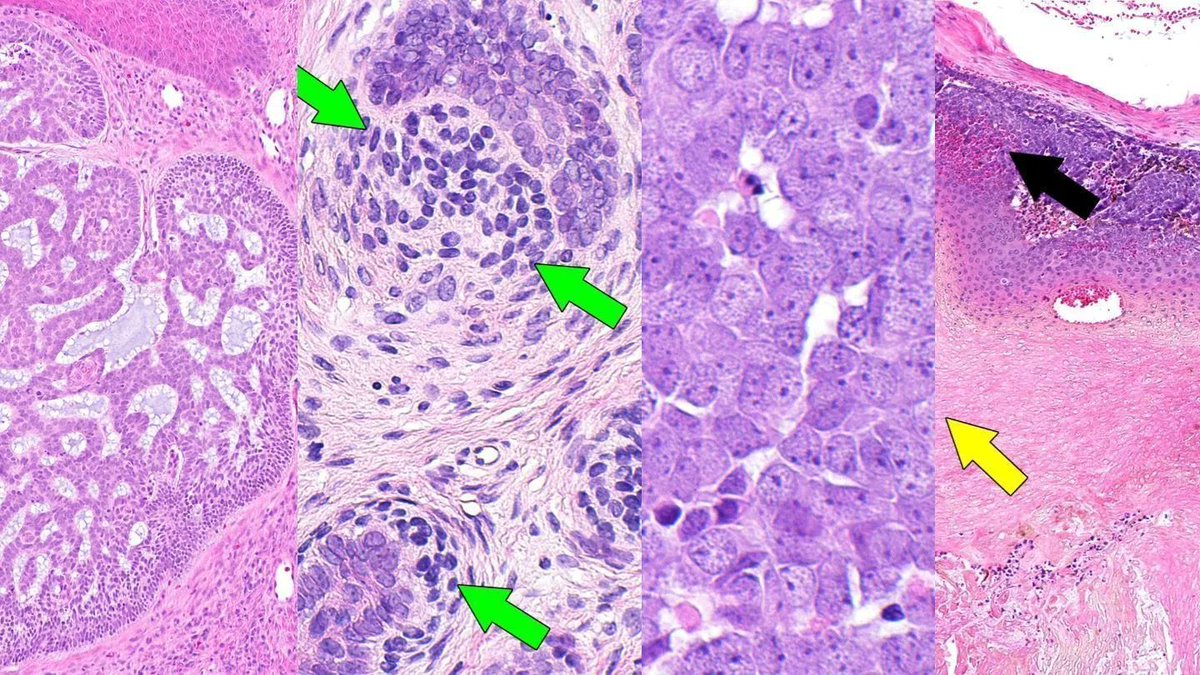

Jerad Gardner, MD on Twitter "RT HENRYY_MD Anorectal Basaloid Basal Cell Carcinoma Jerad Gardner — basal cell carcinoma (bcc) arises from the interfollicular or follicular epithelium. — sample pathology report templates for basal cell carcinoma: as the most common human cancer worldwide and continuing to increase in incidence, basal cell carcinoma is associated with significant morbidity. — basal cell carcinoma (bcc) is the most common human cancer worldwide, and is. Basal Cell Carcinoma Jerad Gardner.